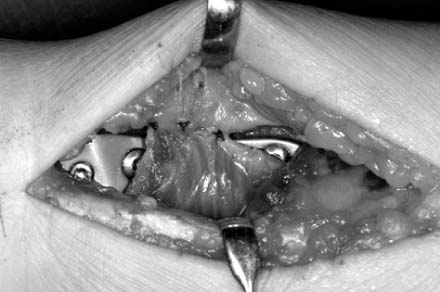

Fig. 10

A dotted line indicates transverse ridge, and the fracture site is exposed after elevation of pronator quadratus.

Fig. 10 A dotted line indicates transverse ridge, and the fracture site is exposed after elevation of pronator quadratus.